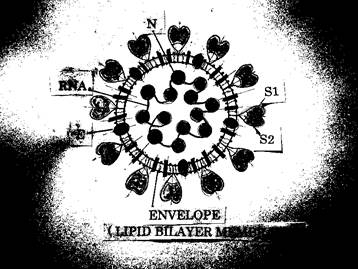

Viral Structure

COVID -19 is an enveloped, positive-sense, single-stranded RNA virus approximately 60 to 140 nm in diameter. The shape is a crown-like appearance under an electron microscope (coronam is the Latin term for crown). The lipid bi-layer envelope of these viruses is relatively sensitive to desiccation, heat, and detergents. The virus spike (S) protein is a large, type1, membrane glycoprotein that contain distinct functional domains near the amino (S1) and carboxy (S2) termini. The S1 firmly binds to the angiotensin converting enzyme 2 receptor in human cell, while the integral membrane S2 portion is required to mediate fusion of viral and cellular membranes.

A viral envelope is the outer most larger. The transmembrane domain of the E protein has been found to alter the membrane permeability.

Nucleocapsid (N) or N protein plays a vital role during virion assembly. The process of virion assembly requires efficient packaging of the viral RNA into the virion. For this, N protein associates with the viral genomic RNA, and together they form the ribonucleoprotein.

N protein has also been reported to bind to human cellar heterogeneous nuclear ribonucleoprotein A1 (hn RNPA1) with high affinity. It may be postulated that interaction COVID-19, N protein with hn RNPA1 may play a role in transcription and replication of viral genome[3,4,5] (Fig.1).

(Fig.1)